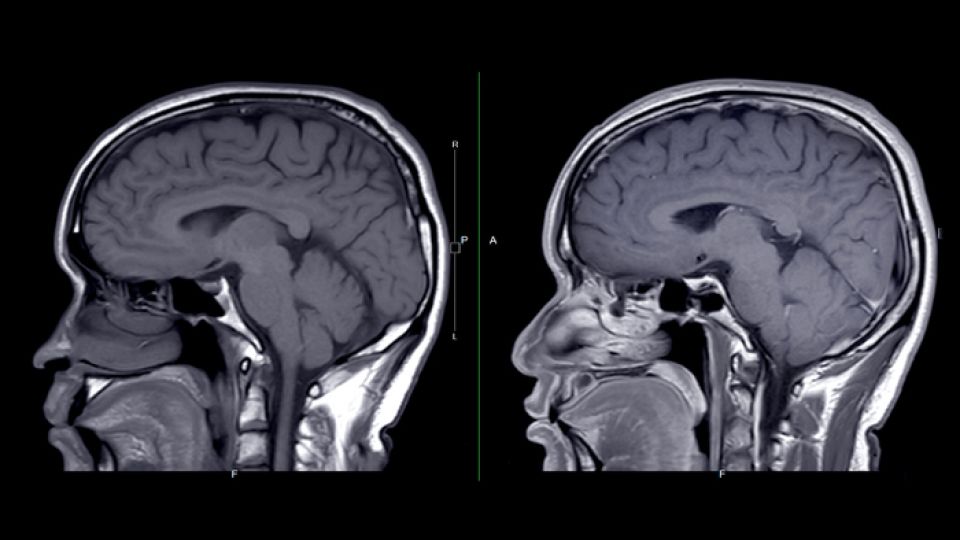

안면위험삼각에 난 상처를 통해 들어온 세균이 혈관을 타고 뇌에 침투할 수 있는 것입니다. 이 경우 안면 정맥과 뇌 사이에 이물질을 거르는 기관이 존재하지 않기 때문에 뇌에 세균 등이 쉽게 침투하게 됩니다.

해면정맥동에 세균이 들어가게 되면 혈전이 형성되는 경우가 생깁니다. 이러한 경우 뇌경색, 더 심해지면 뇌수막염이나 뇌농양으로도 진행될 수 있습니다. 뇌수막염은 뇌 부분에 박테리아에 의한 부종이 발생하는 질병입니다. 뇌농양은 뇌에 침입한 세균에 의해 고름 주머니(농양)이 생기는 질병입니다.